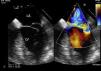

Intraoperative 2D/3D transesophageal echocardiography confirmed rupture of one of the heads of the anterolateral papillary muscle, leading to extensive prolapse of the P1 and P2 segments and causing severe mitral regurgitation (Figures 2 and 3A and B; videos 1, 2 and 3). On surgical inspection, it was observed that the detached muscle head (Figure 4) had become trapped in the left ventricle by a secondary cord attached to the other head. Papillary muscle head reimplantation, mitral annuloplasty with a rigid ring, tricuspid annuloplasty with a Sovering ring and double coronary artery bypass grafting (CABG) (left internal mammary artery to first obtuse marginal and right internal thoracic artery to anterior descending artery) were performed.

Three-dimensional transesophageal echocardiography. (A) Full volume cropped image showing the detached head of the anterior papillary muscle inside the LV (arrow) causing severe prolapse of the posterior leaflet; (B) 3D Zoom of the mitral valve showing prolapse of the P1 and P2 segments. LA: left atrium; LV: left ventricle; Ao: aortic valve; LAA: left atrial appendage.